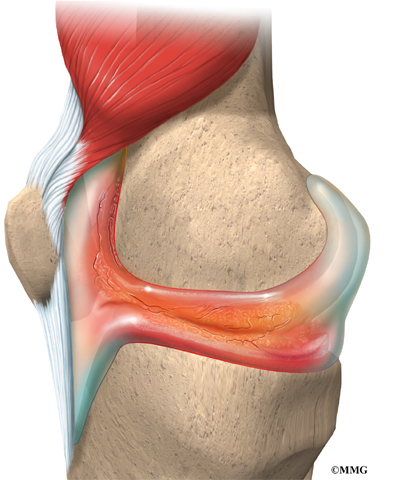

Медицинские состояния: Септический артрит коленного сустава